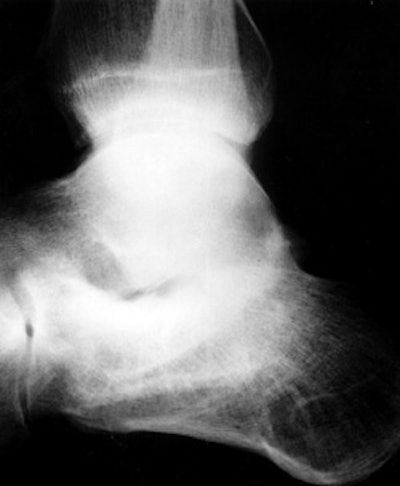

In 96 patients evaluated for arthritis pain, 218 joints were injected (figure 1).

FIGURE 1. (A) Lateral radiograph of a patient with hindfoot pain and the suggestion of subtalar arthrosis.

(B) Sagittal fat-suppressed MR image showing posterior facet arthrosis of the subtalar joint and edema within the sinus tarsi.

(C) The patient undergoing a series of injections with contrast seen in the ankle and sinus tarsi. The ankle injection did not relieve symptoms, the sinus tarsi injection relieved 75% of pain.

(D) Lateral radiograph 10 months after talo-calcaneal fusion and excision of the sinus tarsi contents with a reported 80% reduction in pain.

All joints were injected successfully. Based upon the degree of pain relief from injection, 22 patients were offered surgical treatment and 18 people chose surgical treatment. There were 7 painful ankles and 11 painful feet in 18 patients that had surgical treatment. All of the painful small joints of the foot had arthrodesis, 3 of the painful ankles had arthrodesis, 2 ankles had synovectomy and 2 had replacement arthroplasty. Ten of 11 patients with foot arthrodesis had pain relief similar to that of the injection and 1 patient had approximately 50% pain relief.

The ability to limit the number of joints fused by assessing pain relief from a series of preoperative image-guided arthrograms was also important. All patients have a minimum of 9 months follow-up since surgery. Five of 7 ankle pain patients had relief similar to the injection; one ankle arthroplasty and one arthrodesis patient had 50% improvement, none were worse following surgery. All surgical pathology specimens from the arthrodesis sites demonstrated the pathologic tissue changes of chronic synovitis, degenerative joint disease (i.e., bone and cartilage degeneration), or both.